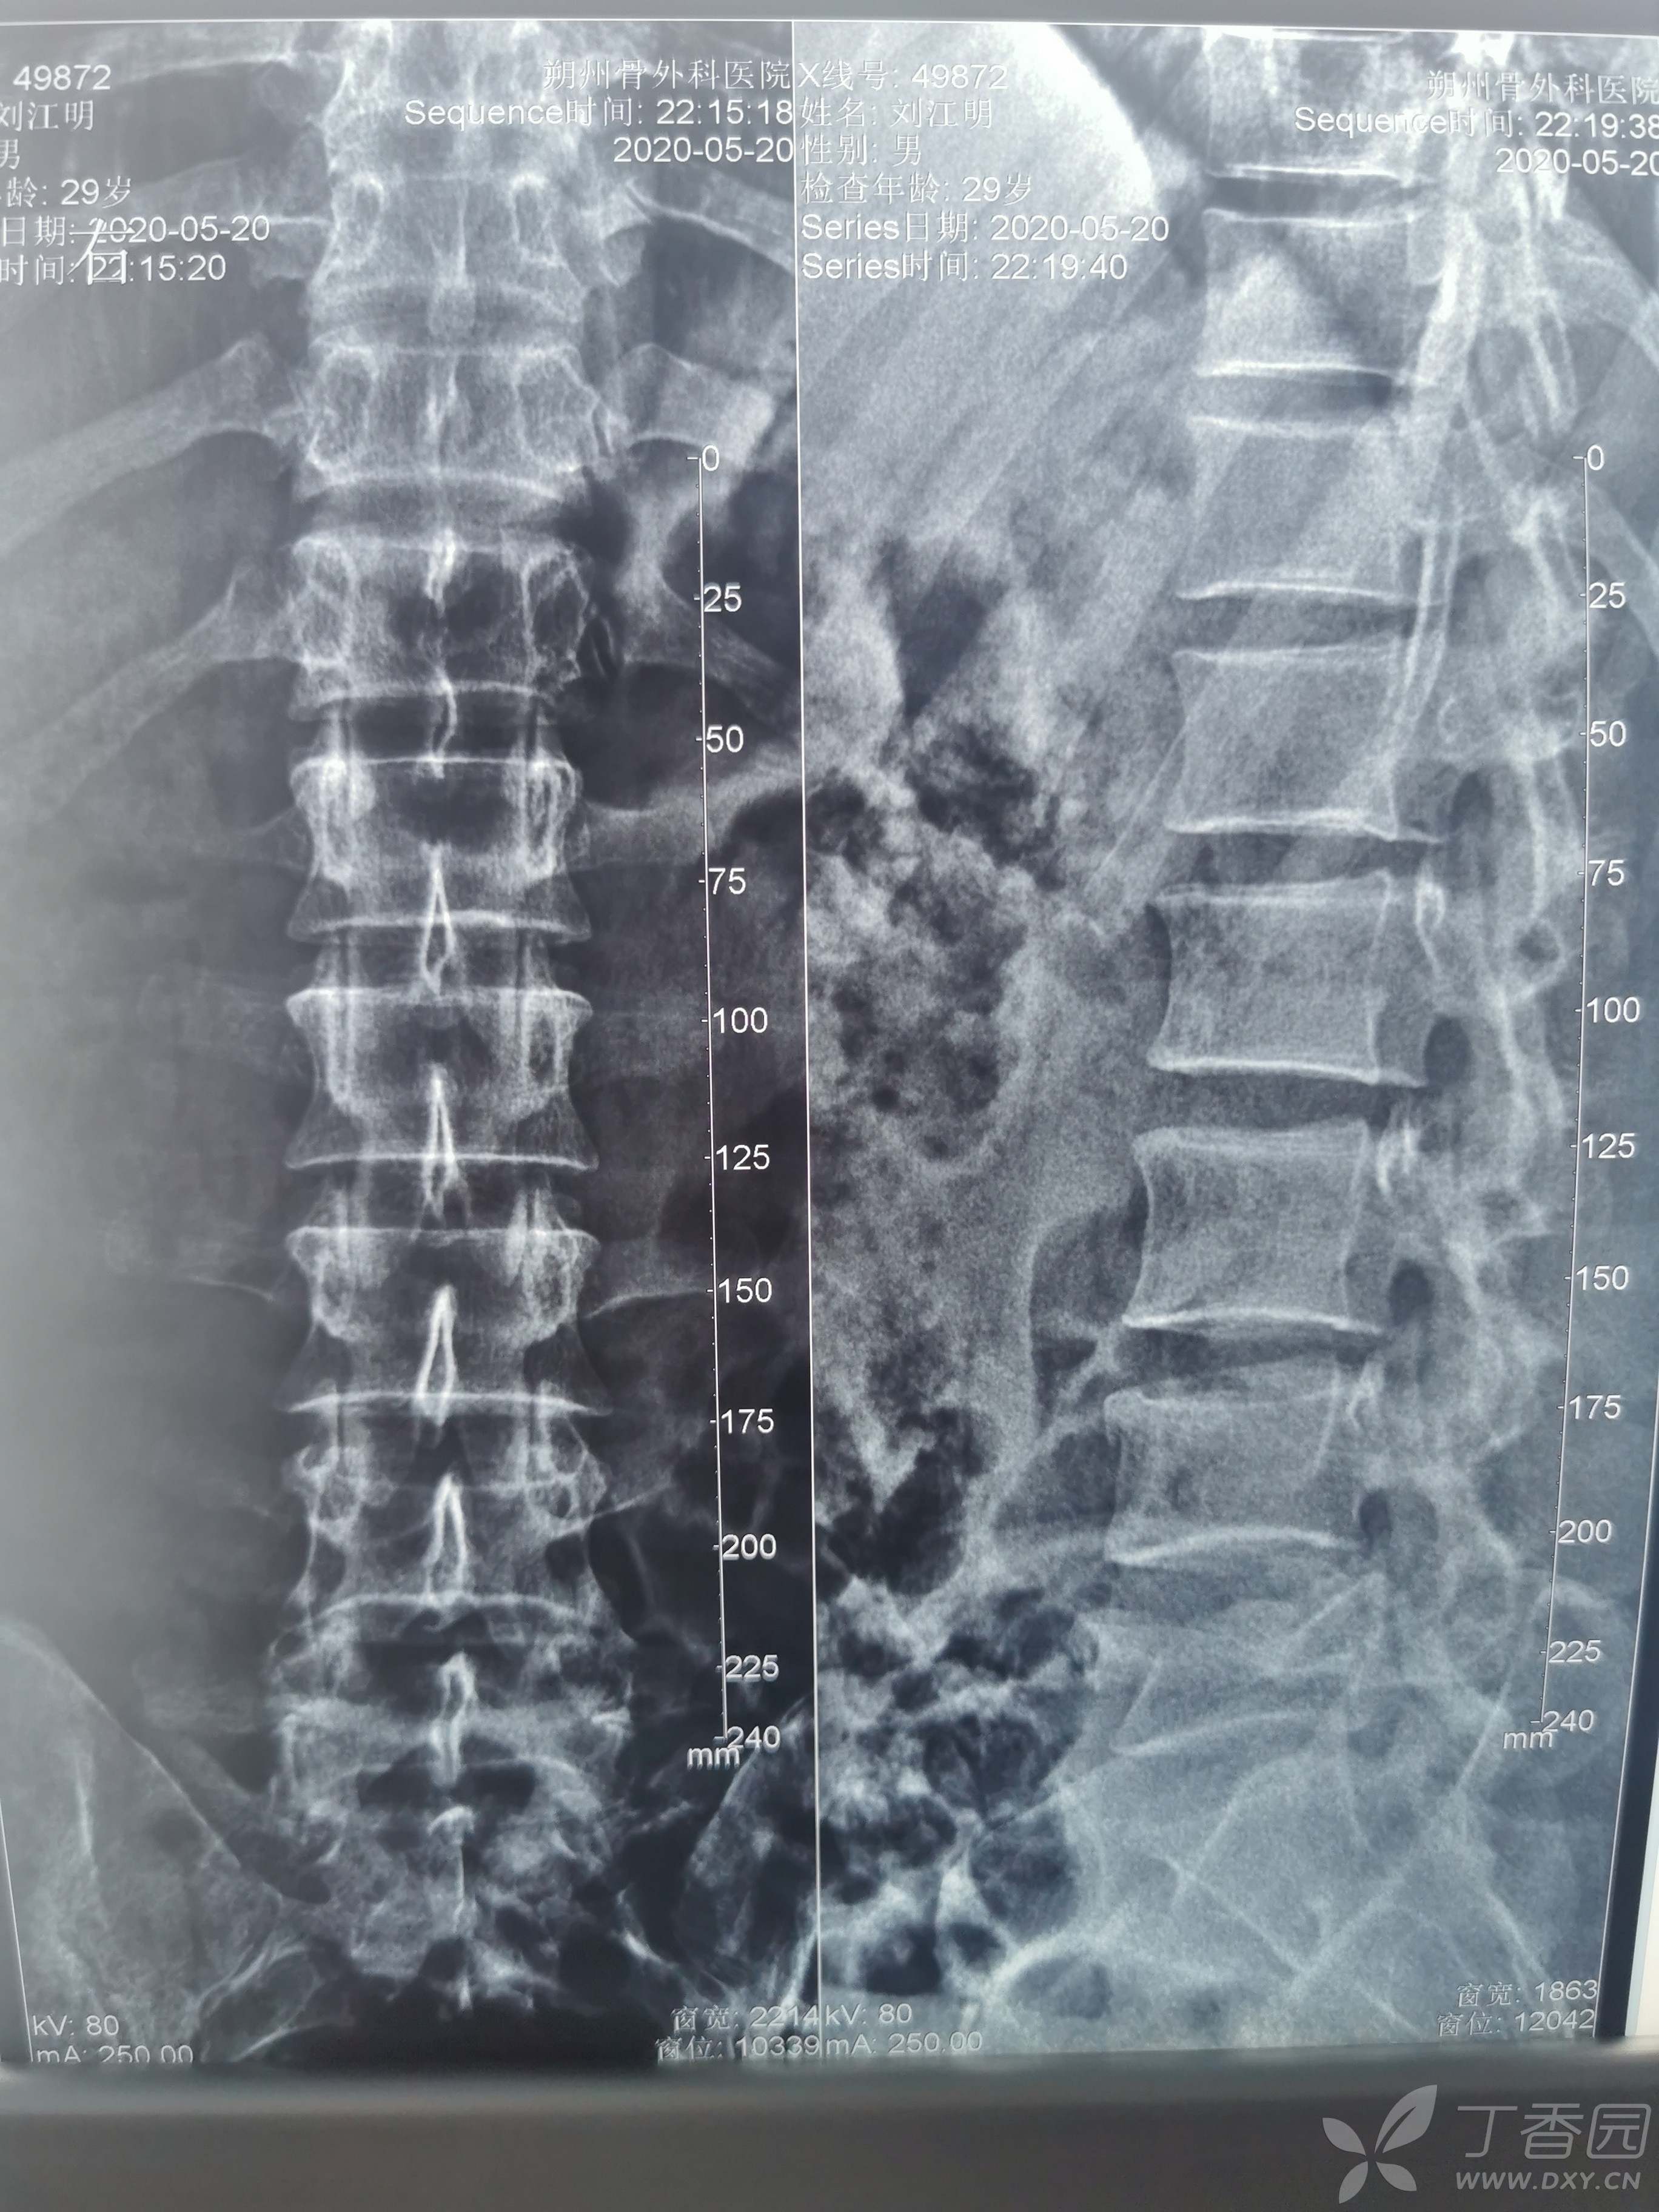

胫腓骨骨折闭合复位带锁钉固定,腓骨钢板固定

患者,男性,54岁,滑倒致伤入院急诊固定